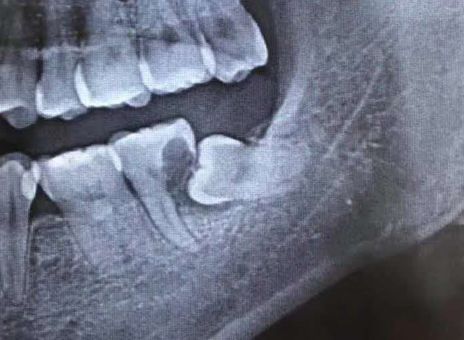

患者张先生2个月前突然发现,自己下颌左侧牙齿,遇凉、热都会剧烈疼痛,甚至不敢用左侧牙齿吃东西,在某口腔门诊钻开牙齿,反复换药治疗几次后仍未见缓解,才想着到大医院看一看。二一五医院口腔科接诊后发现,患者口内下颌最后一颗牙齿上有溢出的白色充填材料,而这颗患牙在几次不当治疗后,已经明显松动,且咬合时剧烈疼痛,患者自述在前期治疗过程中没拍X线片明确病情,接诊医师随即为他安排了口腔CT拍摄。CT发现,在这“摇摇欲坠”的牙齿下,还悄悄隐藏着一颗倾斜的智齿,而这颗智齿,已经几乎“吃光了”它侧方“松动”牙齿的牙根,这才是导致张先生牙疼反复治疗无效的根本原因!

第二位患者同样姓张,但他在25岁的年纪,却已经被智齿疼痛折磨了2年多了。小张自述,自己的智齿疼,并不是“疼起来要人命”的那种,所以才一拖再拖。但近期,小张的下颌右侧牙龈反复长脓包,因担心病变扩大,才终于鼓足勇气走进了口腔科。医师在检查小张口内情况时看到,该患者下颌右侧第二磨牙牙冠表面完整,但在颊侧牙龈位置处,可见约5mm直径的脓包,脓包下,一颗牙冠倾斜部分微微露出的智齿隐约可见,而这两颗牙齿之间,竟有着大量嵌塞的食物,已然形成龋洞!并且第二磨牙周围骨质被破坏严重,牙齿已经是“悬浮”在牙槽窝内,这颗看似完整的牙齿因为智齿给予的阻力和龋洞的存在,其实已经不具有保留价值了,只能和智齿一起被连根拔除。